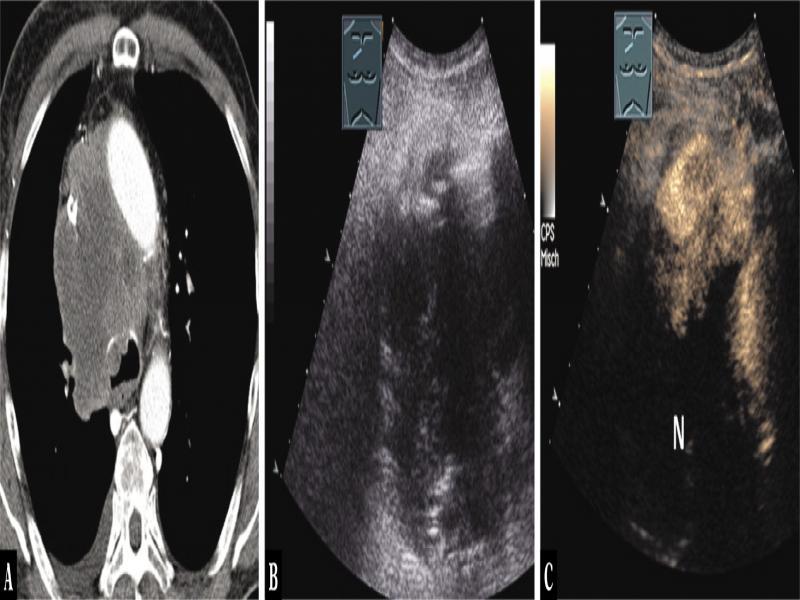

Fig. 4.

A 43-year-old female patient admitted for ultrasound-guided biopsy due to mediastinal tumor (arrow) in the anterior mediastinum as an incidental finding on computed tomography after an intensive care stay (A). Thoracic ultrasound indicated a complex hypoechoic tumor (B), which showed no enhancement on contrast-enhanced ultrasound, as in hematoma (H) (C). A biopsy was not performed due to anamnestic central venous catheter. The tumor showed spontaneous regression